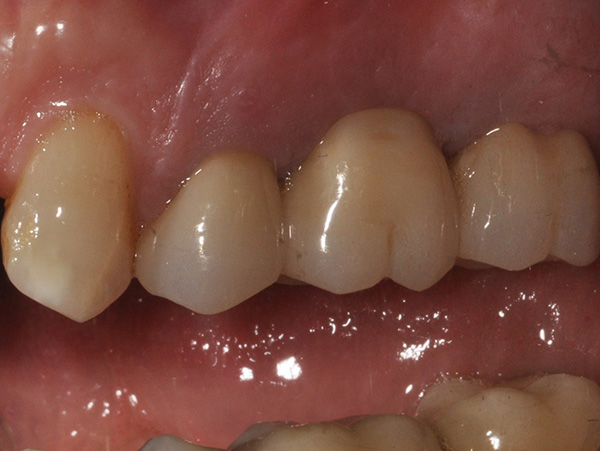

A causa della frattura della radice vestibolare del 24, tramite sondaggio puntiforme e fistola, si è proceduto alla separazione del ponte 24-x-26, conservando l’elemento 26.

L’intervento è stato eseguito dal Dr. Alessando Casolino (Bologna) dello Studio del Dr. Casolino e la protesi è a cura dell’Odt. Massimo Venerato (Lab odontotecnico C.P. Dental) su MUA tipo A dritti dell’altezza di 1 mm.